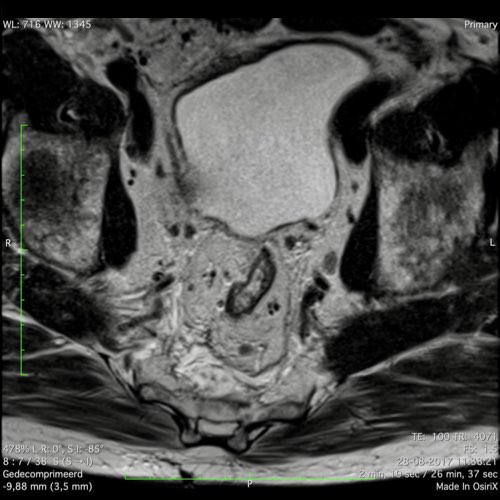

Hình ảnh

Các hình ảnh được cung cấp cho thấy ung thư biểu mô tế bào nhẫn với tình trạng dày lan tỏa thành trực tràng, hình ảnh bia bắn điển hình, và sự xâm lấn mỡ mạc treo trực tràng.